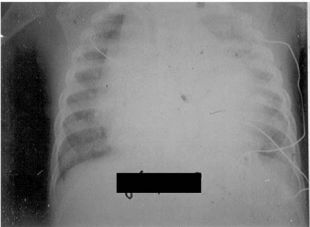

86 5 歲男童正常發育,過去無特定疾病,且有定期健兒門診及接受預防針注射之紀錄。自今天早上開始 發燒,下午有哭鬧且出現前胸痛,晚間到兒科急診,醫師發現心音聽不太到,且測量脈搏約每分鐘 150 下,血壓 80/50 mmHg,經直立胸部 X 光檢查,結果如下圖,其最可能的診斷為何? (A) 心室中膈缺損疑似合併左心衰竭(ventricular septal defect with left heart failure) (B)心肌炎疑似合併心室頻脈(acute myocarditis with ventricular tachycardia) (C)急性心包膜炎疑似合併心包填塞(acute pericarditis with cardiac tamponade) (D)肺動脈高壓症疑似合併右心衰竭(pulmonary arterial hypertension with right heart failure)